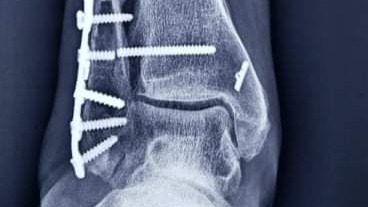

Brandi broke her leg in 3 spots (trimalleolar fracture) in Oct 2020 outside of the states and the dr opted to not do surgery.. after 12 weeks in a cast, she was released with no further care.. she sought the guidance of 2 different physical therapists. It was the 2nd PT who told her to seek a 2nd opinion with another ortho. The Dr. said it was too late to do the surgery she needed since her bones were starting to fuse. She started looking for someone in States. She found a surgeon that would see her via zoom and he agreed she needed to fix her ankle asap.. After making everything happening to get the first surgery (she got a loan because insurance would only cover 40%) they did a total ankle reconstruction and found she had a dislocated ankle bone as well. She healed great and started walking mid August. In the end of Sept, the screw going through both bones broke which is causing her a lot of pain. She saw her surgeon in end if January who told her she has scarring behind the plate and arthritis in her ankle.. He needs to remove her hardware and scrape out her ankle if he can. It is her only hope at less pain.